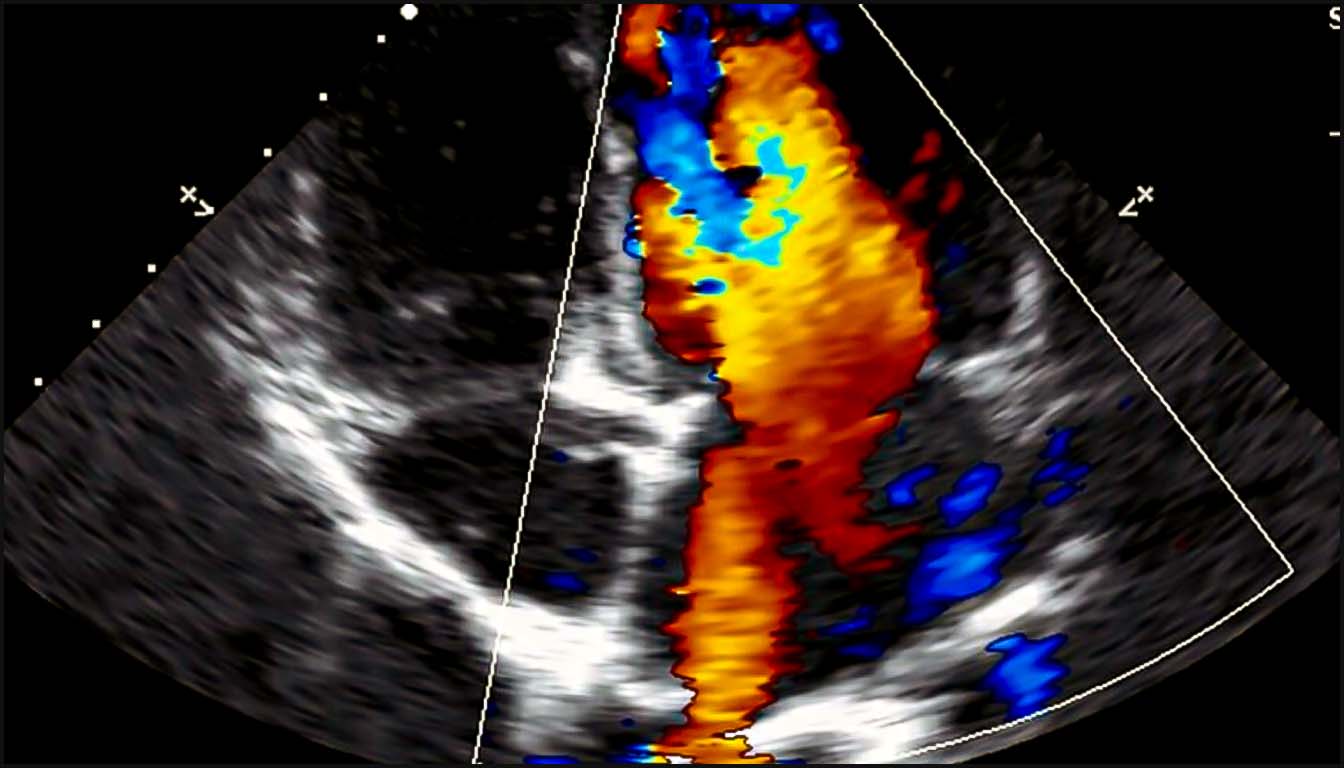

III. Apports du Doppler Couleur et Pulsé

Le Doppler est indispensable pour valider l’anatomie et évaluer la fonction.

• Flux Rétrograde : Un flux inversé (bleu au lieu de rouge ou vice-versa) dans l’isthme aortique ou le canal artériel est un signe de cardiopathie ducto-dépendante, comme une atrésie aortique ou pulmonaire.

• Régurgitations Valvulaires : Une régurgitation tricuspide holosystolique est un marqueur important de CC structurelle et d’aneuploïdie, particulièrement au premier trimestre. Une régurgitation mitrale sévère peut accompagner une sténose aortique critique.

• La coupe des trois vaisseaux et de la trachée (3VT) : Cette vue est cruciale pour évaluer les voies d’éjection et les arcs vasculaires. Normalement, l’isthme aortique et le canal artériel convergent à gauche de la trachée pour former un signe en “V” avec un flux antégrade et non turbulent. Le Doppler couleur facilite la détection précoce de la transposition des gros vaisseaux (TGV), où les vaisseaux apparaissent parallèles, et des anomalies de l’arc comme l’artère aortique droite, signalée par un signe en “U” entourant la trachée.

L’ajout du Doppler couleur à l’évaluation de la 4C et des voies d’éjection augmente significativement la sensibilité du dépistage, passant d’environ 42 % à 78 % dans les populations à bas risque.